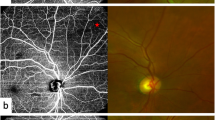

Recent advances like OCTA permit the quantification of macular capillary modulations across the superficial and deep layers, in response to PRP. This finding has not been reported by previous studies, which were limited to the study of large vessel hemodynamics. Therefore, we performed serial follow-up OCTA imaging to compare with baseline measurement by 12 months post PRP. Fawzi et al.24 reported an overall increase in the OCTA flow metrics of all capillary layers in the macula, 6 months after PRP. Mirshahi et al.25 reported that foveal vascular density, measured using OCTA, increased 3 months after PRP. In the current study, decrease of PD and VLD, 1 month after PRP implies the effect of acute inflammation of the retinal tissue, subsequent to laser treatment. Consequently, we observed an overall increase in PD and VLD at both capillary plexuses, 12 months after PRP and there was a significant difference, when compared to the measurements taken 1 months after PRP. Possible underlying mechanism for the improved flow in the remaining macular capillaries could be re-establishment of macular microvasculature, from regression of peripheral neovascularization or intraretinal microvascular abnormalities (IRMA). A representative case of PDR treated with PRP was shown in Fig. 3A. As mid-peripheral neovascularization and IRMA disappeared, capillary perfusion improved and NPA decreased after 6 months (Fig. 3B). Conversely, our analyses did not reveal any significant alteration in the FAZ area following PRP, which was consistent with previous literature25,26. Lorusso et al.26 in a similar study, investigated the alteration of OCTA parameters following PRP. Contradictory to our results, they did not observe any changes in the PD and FAZ area. This discrepancy can be due to the different methods employed to measure OCTA parameters and the diverse follow-up periods. Primarily, we focused on the macular microvascular status, without considering the well-known vasoconstrictive effect on larger vessels, following PRP treatment. By excluding the major branches of retinal vessels on OCTA, we calculated the capillary density selectively as the percentage of vascular voxels on en face projection angiograms. Furthermore, the duration of follow-up in the current study extended up to 12 months after PRP, compared to previous studies with relatively shorter duration of follow-ups, such as one to 3 months after PRP. In the present study, the measured values of PD and VLD increased continuously, across the 12-month follow-up period, and the difference was found to be statistically significant.

(A) Representative SS-OCTA images for PDR cases that had mid-peripheral neovascularization and IRMAs (red circles). (B) Three months after PRP treatment, neovascularization and IRMAs disappeared and re-established with retinal capillaries. Overall nonperfusion area (blue color coded) reduced and capillary perfusion density and vessel length density improved after PRP.